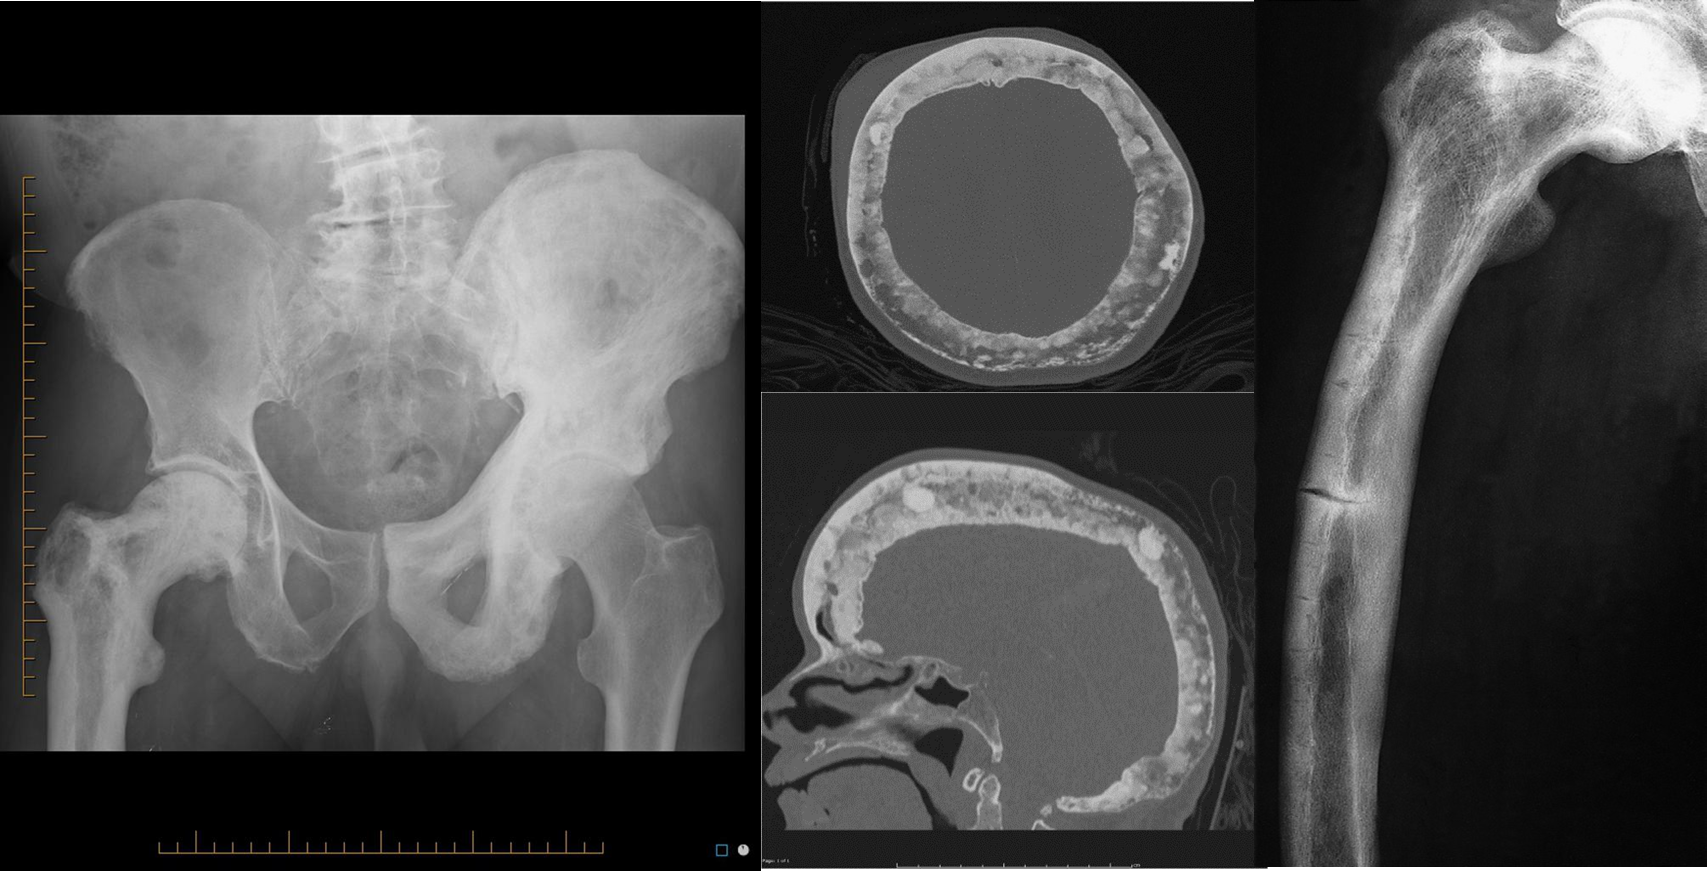

• Thickening of the trabeculae and of the cortex.

• Increased bone density.

• Enlargement of the affected bone A) The classically described radiological appearances are sclerotic expanded bone with a coarsened trabecular pattern

B) Axial & sagittal reformat of CT demonstrating coarse trabeculae, and enlargement of the skull bone

C) Paget’s disease showing incomplete fractures of the lateral aspect of the femur. Note the marked thickening of the cortex and bowing of the femur.